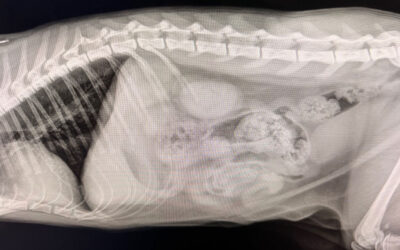

Clearwater Veterinary Ultrasound vs X-Rays

When it comes to diagnosing health issues in dogs, cats, and other companion animals, pet owners often wonder about the difference between veterinary ultrasound vs x-rays. Understanding how each tool works—and when a veterinarian might recommend one over the other—can help you feel more confident in your pet’s care.